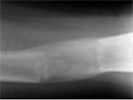

Femoral lengthening with Ilizarov frame in-situ

Progress

Restoration of leg length and good bony union